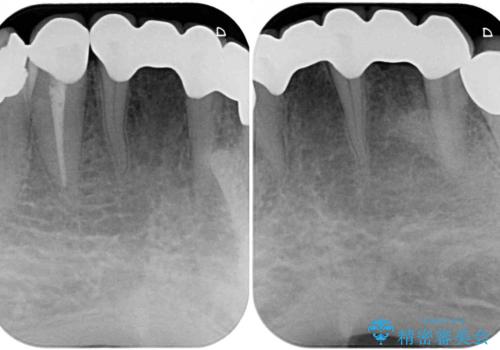

- 乳歯や矮小歯が多くある前歯部の審美障害が気にして来院された患者様です。

上顎の矮小歯は隙間が多く、歯軸の傾斜も大きかったため、部分矯正により補綴治療前に歯の位置を整えることとしました。

下顎の乳歯は支台歯として機能することは困難と思われたので、事前に抜歯をし、上顎の矯正治療終了のタイミングに合わせて、セラミックブリッジにて補綴治療することとしました。

前歯部はディープバイトという、上顎前歯が下顎前歯に深く覆い被さる咬合であったので、理想的には全顎矯正が必要となりますが、今回は患者希望により前歯部のみの部分矯正で対応しました。そのため下顎犬歯の神経を取り除くことになってしまったのは心残りであります。